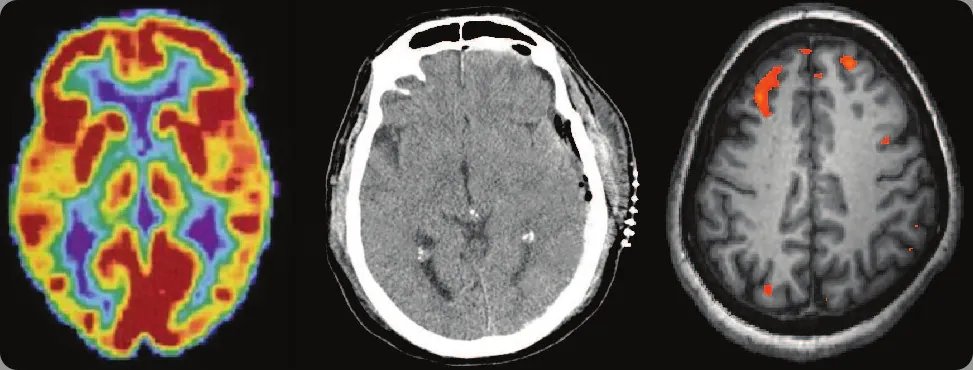

Ilustracja 3.1 W zależności od wyboru technik obrazowania otrzymujemy różne informacje na temat funkcjonowania mózgu. Od lewej: obraz uzyskany metodą pozytonowej tomografii emisyjnej (PET), tomografii komputerowej (TK) i czynnościowego rezonansu magnetycznego (fMRI). (Źródło: obraz po lewej: modyfikacja za amerykańskim Departamentem Zdrowia i Usług Społecznych, Narodowy Instytut Zdrowia (National Institutes of Health, NIH); obraz środkowy: modyfikacja za „Aceofhearts1968”, Wikimedia Commons; obraz po prawej: modyfikacja pracy Kim J., Matthews N. L., Park S.).

Czy zdarzyło ci się kiedyś rozłożyć jakieś urządzenie na czynniki pierwsze, żeby dowiedzieć się, jak działa? Wielu z nas kiedyś tak zrobiło, żeby naprawić zepsuty mechanizm, albo nawet z czystej ciekawości. Wnętrze maszyny często bardzo różni się od tego, co nazywamy interfejsem użytkownika. Przecież zwiększając głośność w smartfonie, mało kto na co dzień myśli o obwodach i mikroczipach; chcemy tylko uzyskać odpowiednie natężenie dźwięku. Podobnie jest z ludzkim ciałem. Wewnętrzne mechanizmy często różnią się od zewnętrznych przejawów ich działania. Zadaniem psychologów jest odnalezienie związku między tym, co na zewnątrz, a tym, co w środku, np. odkrycie, w jaki sposób wyładowania milionów neuronów stają się myślą.

W tym rozdziale spróbujemy wyjaśnić biologiczne mechanizmy warunkujące ludzkie zachowania. Te fizjologiczne i anatomiczne fundamenty stanowią podstawę wielu dziedzin psychologii. Z tego rozdziału nauczysz się, w jaki sposób genetyka wpływa zarówno na naszą fizjologię, jak i na cechy psychiczne. Poznasz budowę i działanie układu nerwowego. Na koniec dowiesz się, jak współdziała on z układem wewnątrzwydzielniczym.